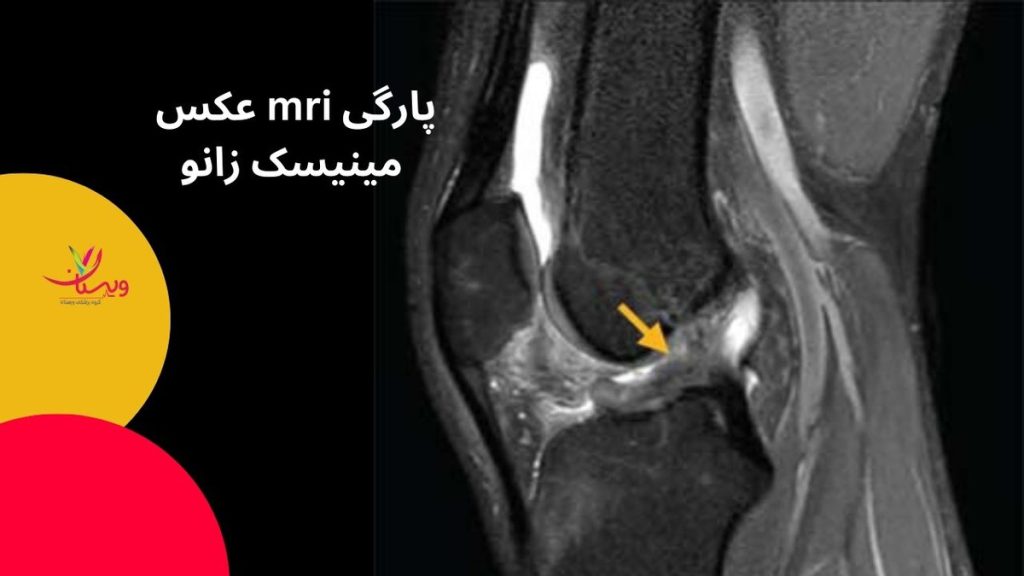

عکس mri پارگی مینیسک زانو